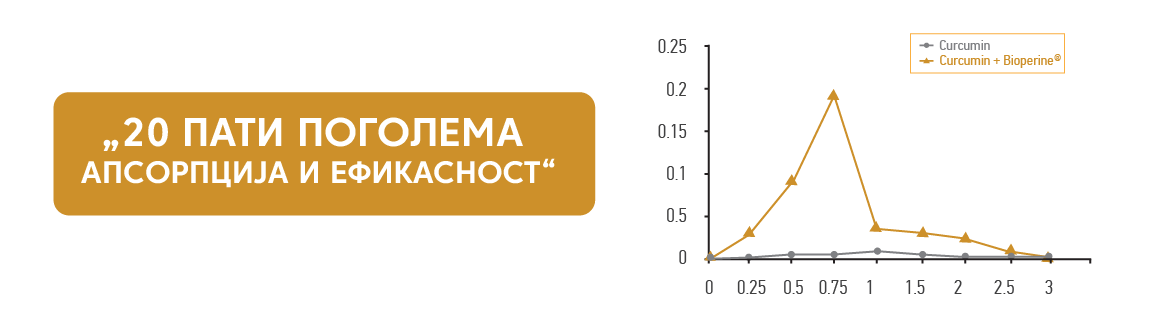

Možete pronaći suplemente kurkume u obliku tečnosti, kapsula ili praha. Važno je odabrati kvalitetan proizvod. Količina, kvalitet i čistoća suplemenata kurkumina mogu se razlikovati od brenda do brenda. Generalno se preporučuje doza između 500 mg i 1000 mg. Međutim, ove doze se mogu razlikovati od brenda do brenda, tako da je važno pratiti etiketu proizvoda. Važno je odabrati pouzdane brendove. Stručni tim nutricionista, farmaceuta, lekara i tehnologa Natura Therapi detaljno je analizirao farmakokinetička svojstva kurkumina, dostupnu tržišnu ponudu i zdravstvene potrebe građana i na taj način kreirao CURCUMACTIV, dodatak ishrani koji sadrži Curcumin C3 Complex® i druge biljne ekstrakte. , u kombinaciji sa Bioperine® ekstraktom paprike i nepromenjen je za smirivanje upale praćene bolom i što je najvažnije bez neželjenih efekata. Možete ga pronaći u prodavnicama Natura Therapy ili naručiti na mreži preko Naturatherapy.rs.